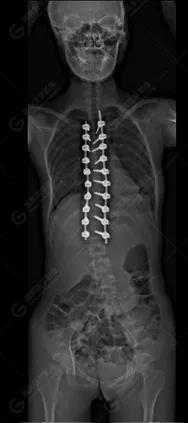

15歲女性,發(fā)現(xiàn)特發(fā)性脊柱側(cè)彎3年,于2019年1月23日來到廣東高尚醫(yī)學(xué)影像診斷中心行EOS檢查,2019年2月行手術(shù)治療后多次到中心行EOS復(fù)查。

2019-02-01

本例患者胸椎右側(cè)彎,Cobb角(T6/T12)為47°,遂行手術(shù)矯正治療。術(shù)后多次隨訪的Cobb角(T10/L3)為12°-15°之間,較術(shù)前明顯縮小。